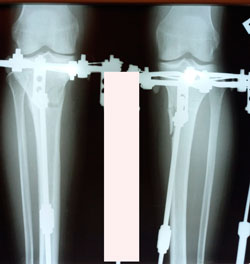

Исходник - 36 лет.

Дата операции - 12.01.2021